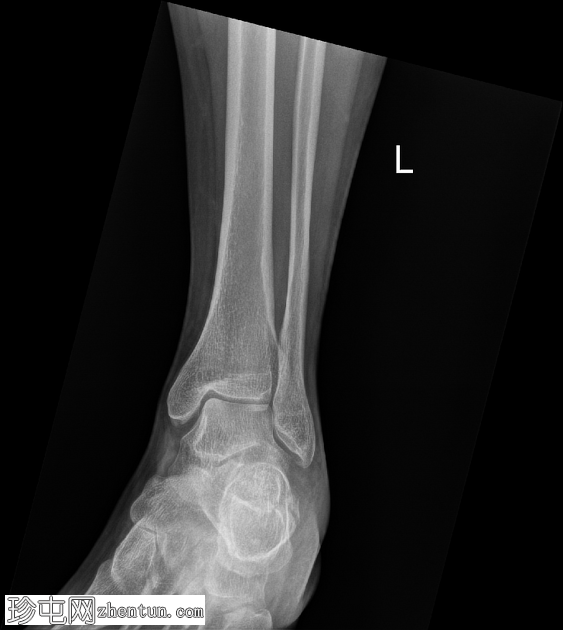

侧位片

左侧跟骨关节内粉碎性骨折。骨折线贯穿跟骨体,累及并破坏距下关节后关节面,并沿跟骨外侧可见一处骨折。骨折始于距下关节中央,向下向后延伸。跟骨整体高度降低,后关节面凹陷,Böhler角变平,Böhler角明显减小,提示后关节面凹陷。

距骨、舟骨以及外踝和后踝均完整,踝穴和韧带联合完整。距下关节和跟骰关节未见脱位。软组织肿胀亦可见。

跟骨骨折是跗骨中最常见的损伤,通常由轴向负荷力引起,例如高处坠落或高强度冲击创伤。本例左侧跟骨的侧位片和轴向片显示,关节内粉碎性骨折延伸至距下关节后关节面,伴有高度降低和后关节面凹陷。

Böhler角(由跟骨前后关节面连线的交点定义)显著减小(约5-10°,正常值为20-40°)。Böhler角的减小反映了后关节面的塌陷,并提示跟骨结构性损伤严重。